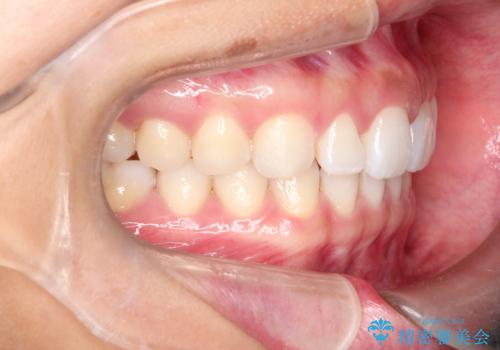

すきっ歯のインビザラインによる目立たない矯正

- すきっ歯を治したいとのことで来院されました。

上下ともに前歯に隙間がありました。

目立たない装置をご希望のためインビザラインで矯正治療を行うこととしました。

使用時間を守っていただけたので、スムーズに治療を終わることができました。